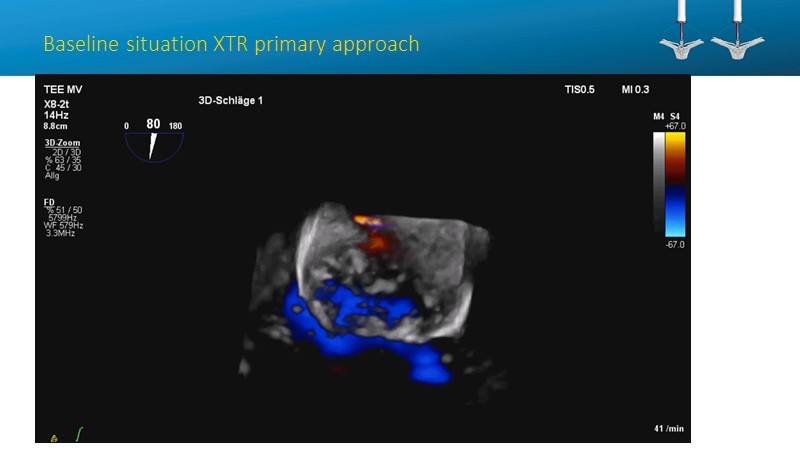

- To learn how will product innovation (Mitraclip NTR / XTR) drive improvement in procedural and clinical outcomes (EXPAND)